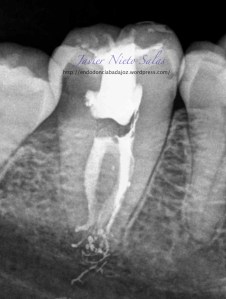

Empezaremos con el primer caso, un 4.7, se trata de una necrosis con afectación periapical.Ante las pruebas diagnósticas, nos fijamos en una fístula muy coronal, un sondaje vestibular puntual, esto nos hace pensar en un diagnóstico diferencial con un Sindrome de Diente fisurado. Sin aparente linea de fisura coronal, no vemos, con la ayuda de la magnificación, linea de fisura, lo que no nos descarta definitivamente que se trate de este síndrome de fisura, pues como ya sabemos pueden aparecer en diferentes tramos de la pieza, clasificando así los diferentes tipos.

Realizamos el tratatamiento de conductos con la sospecha del causante de la necrosis es una fractura vertical, pero no hemos podido ver la linea de fisura.

Se trataría de una cámara pulpar Tipo Ic según la clasificación por el método de Min:

El sistema de Obturación sería con condensación vertical.